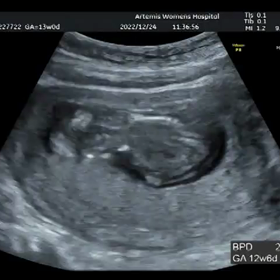

妊婦検診 13w0d 初の3D、4D動画